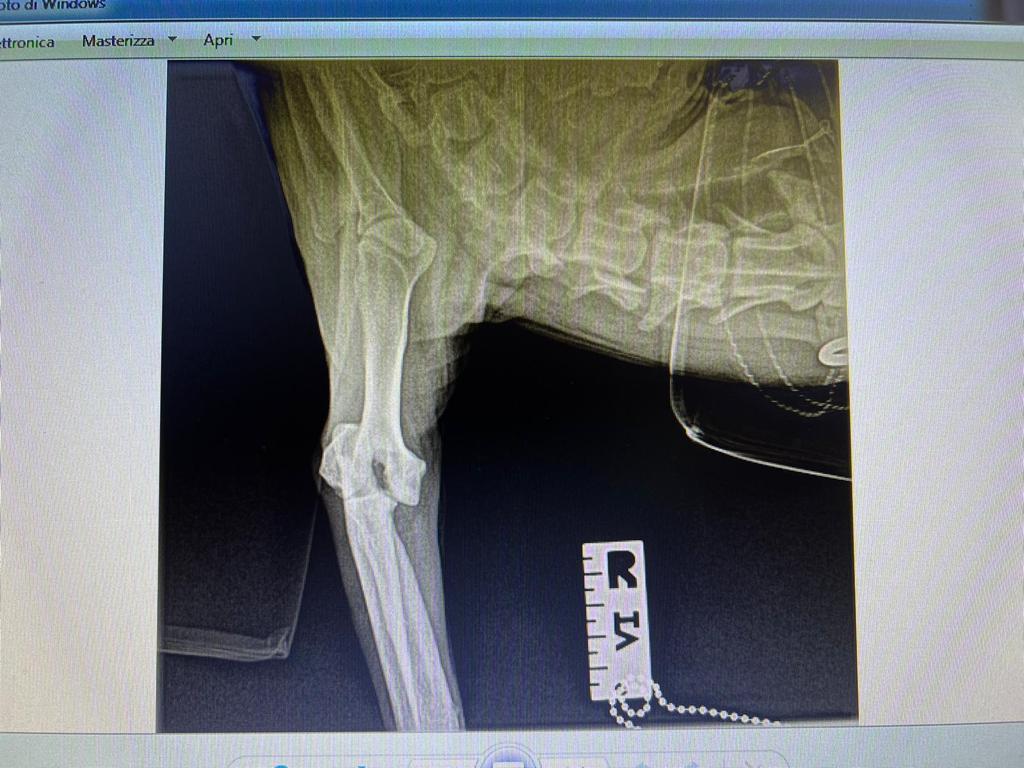

Rüde, Mischling, 3 Jahre, Vermittelt, stammt aus Italien, TierNr. 5213

Bullo

Mischling

3 Jahre

Rüde